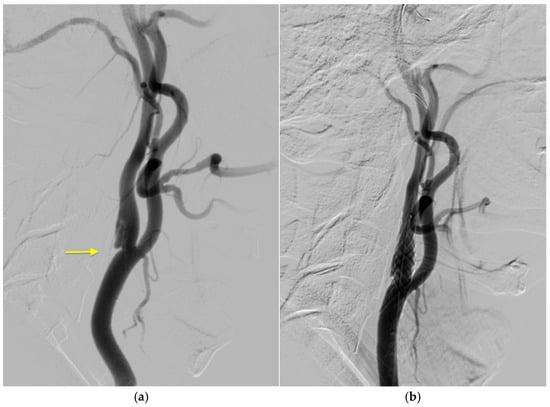

2. Case History